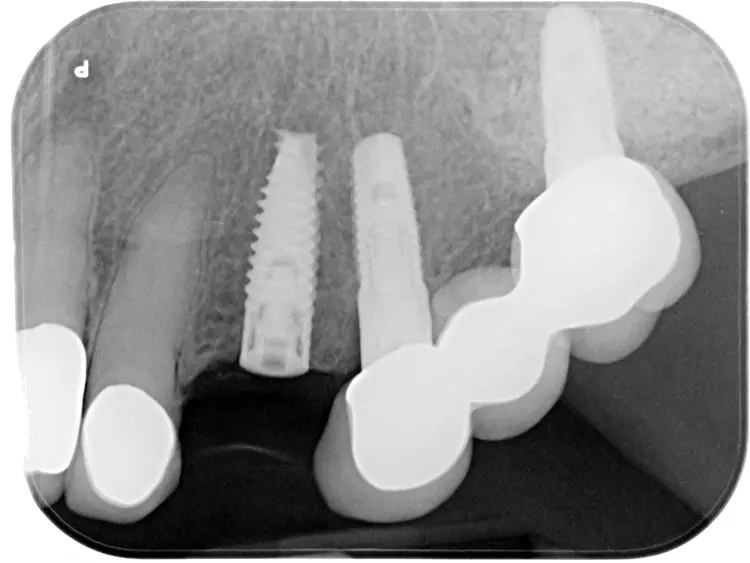

Dabei wurde die beabsichtigte Situation im Vorab per Wax-up simuliert. Beim Entfernen der Altkrone 21 wurde ersichtlich, dass ein Titanabutment eingesetzt wurde, an dem sich Konkremente und Zementreste befanden, die zu einer marginalen Mukositis am Implantat führten.

Die Fraktur des stark elongierten Zahnes 21 war für den Patienten der Ausgangspunkt, sowohl die Front des Ober- als auch des Unterkiefers prothetisch überarbeiten zu lassen. Dabei wurde der frakturierte Zahn 21 durch ein navigiert eingesetztes Sofortimplantat ersetzt, während die verschachtelt stehenden Zähne 12 und 42 durch eine Brückenversorgung korrigiert wurden (Abb. 4a-j).